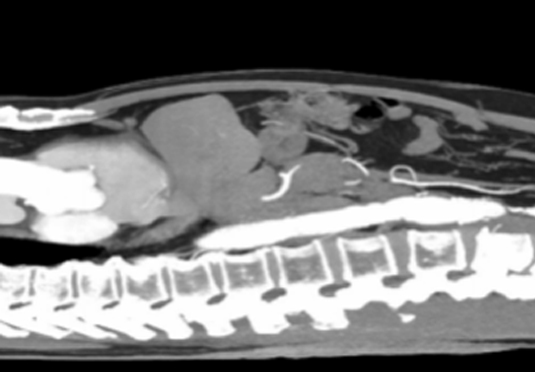

• 微創射頻消融術

適用于微創射頻熱消融術治療患者,引進權威醫療團體輔助引流。

微創射頻消融術